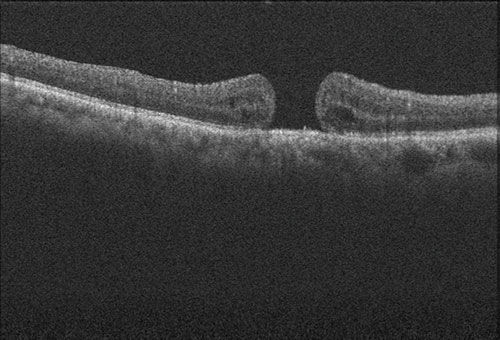

黄斑円孔